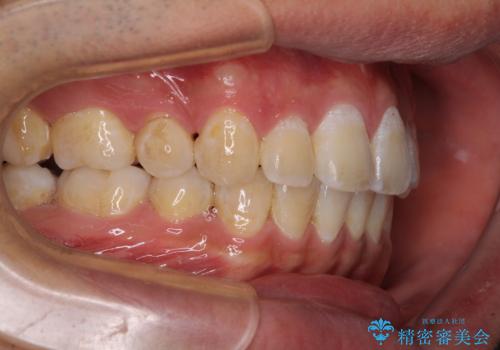

奥歯の咬み合わせを改善したいため、治療期間が長くなりましたが、患者様には辛抱強くお付き合いいただきました。

上下の正中を合わせることもでき、患者様には大変満足していただきました。